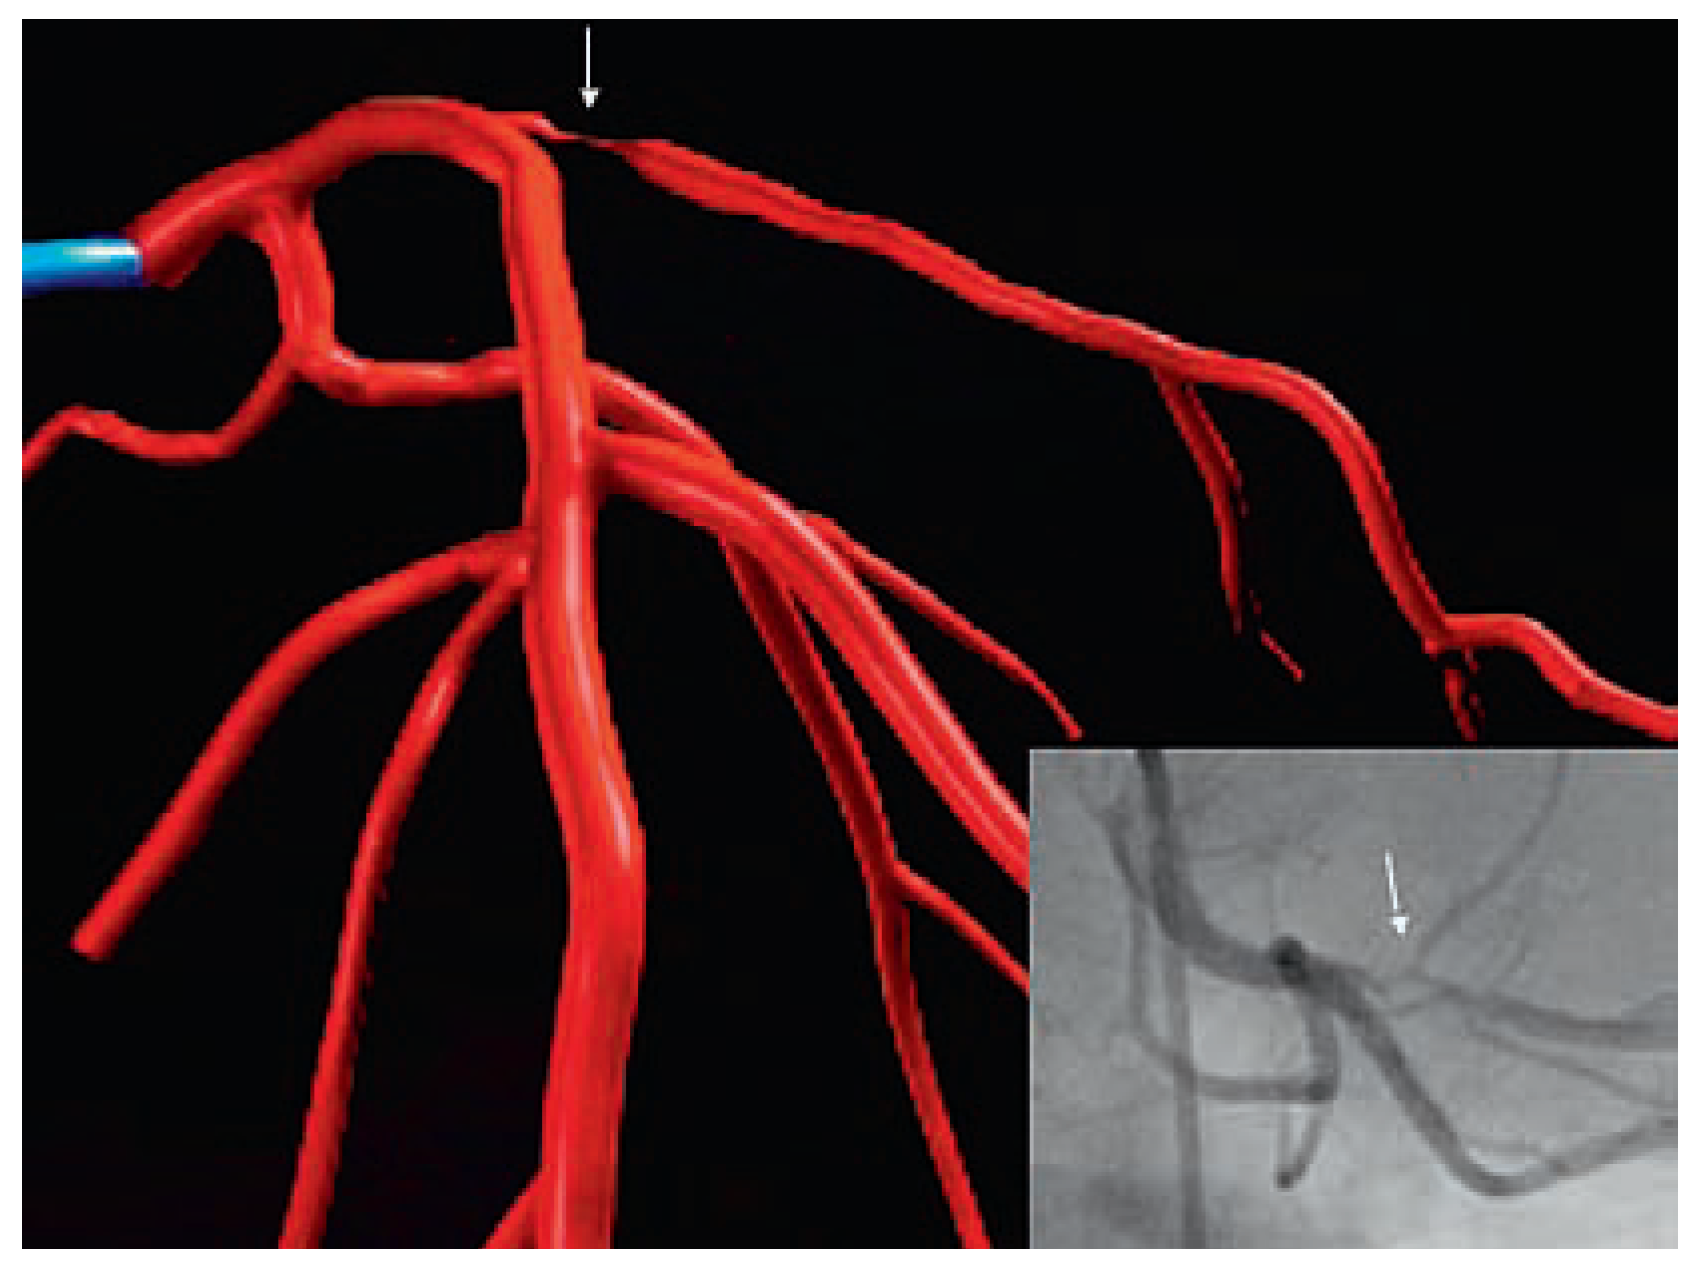

Selective coronary angiography started on October 30th, in 1958, when Mason Sones inadvertently injected dye directly into the right coronary artery of a patient rather than into the ascending aorta as customary at the time (Figure 1) [1]. The quality of the picture was certainly not up to today’s standards. Nonetheless, it is superior to the current resolution of computerised tomography (CT) angiography.

Figure 1. First selective coronary angiogram of 1958.